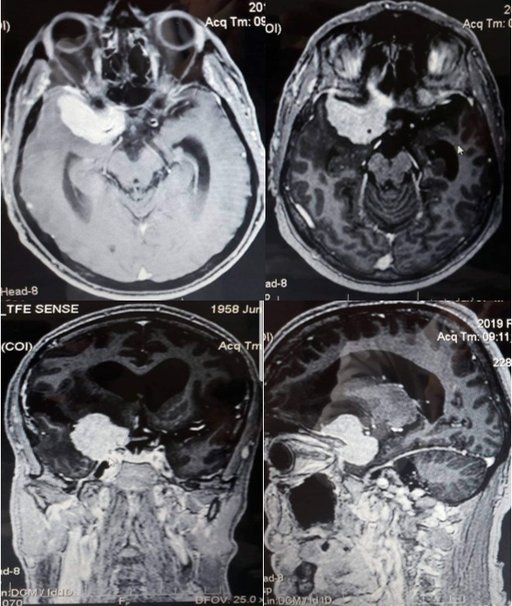

Пацієнт житель м. Тернополя звернувся з скаргами на постійний головний біль, зниження гостроти зору, головокружіння, періодичну нудоту, неконтрольований сечопуск, фокальні епінапади. Проведено дообстеження МРТ голови з контрастуванням (1,5 Т), КТ голови з контрастуванням для виявлення локалізації та співвідношення до оточуючих структур, кровопостачання пухлини.

Пухлина видалена тотально (в товщі пухлини проходили передня та середня мозкові артерії, задня сполучна артерія та передня хоріїдальна артерія), також виконана декомпресія канала зорового нерва. Для адекватного доступу використовувався Neuro High Speed Drill краніотом з мікробороми.